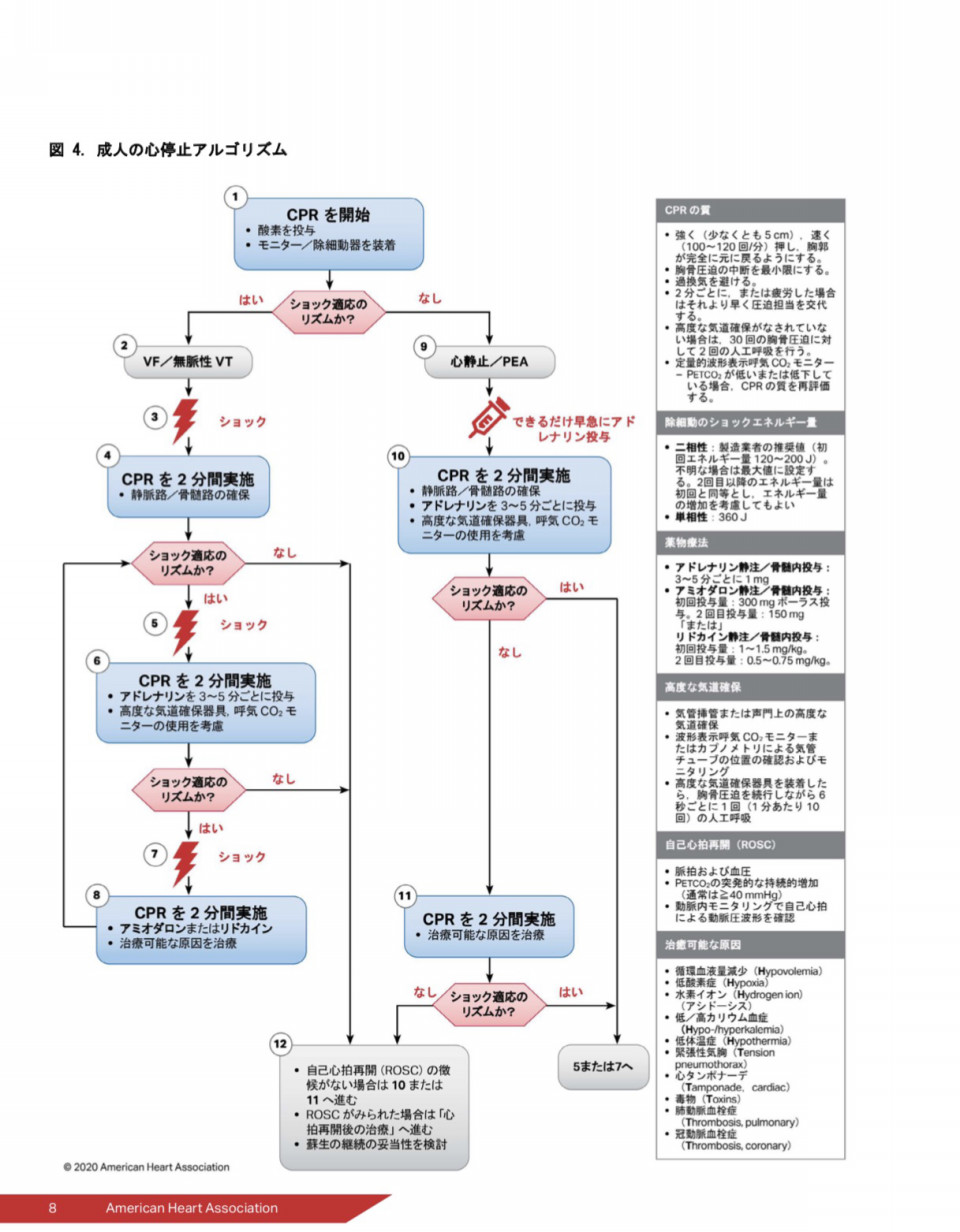

喜多見チーフDrより指示

全身麻酔下による緊急手術

輸液

FFP(新鮮凍結血漿)輸血準備

開腹手術にて動脈が3箇所傷あり止血処置

すぐアドレナリン投与ができなかったため救出後MERカーへ搬送

アナフィラキシーショック状態

気管内挿管

アドレナリン投与

気道閉塞が強くアンビュー(BVM)での換気不十分

希釈したアドレナリンを気管内注入

(1:10,000溶液3〜5mlを生理食塩液10mlに希釈)

アンビューでの換気良好となりSPO2上昇にて症状軽減

病院へ搬送